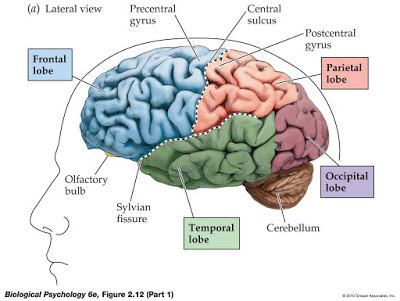

It all started three months before. The headaches. I went to my local General Practitioner, looking for an explanation for the constant throbbing behind my eyes in the frontal lobe, going right through to the back of my head to the cerebellum.

It all started three months before. The headaches. I went to my local General Practitioner, looking for an explanation for the constant throbbing behind my eyes in the frontal lobe, going right through to the back of my head to the cerebellum.